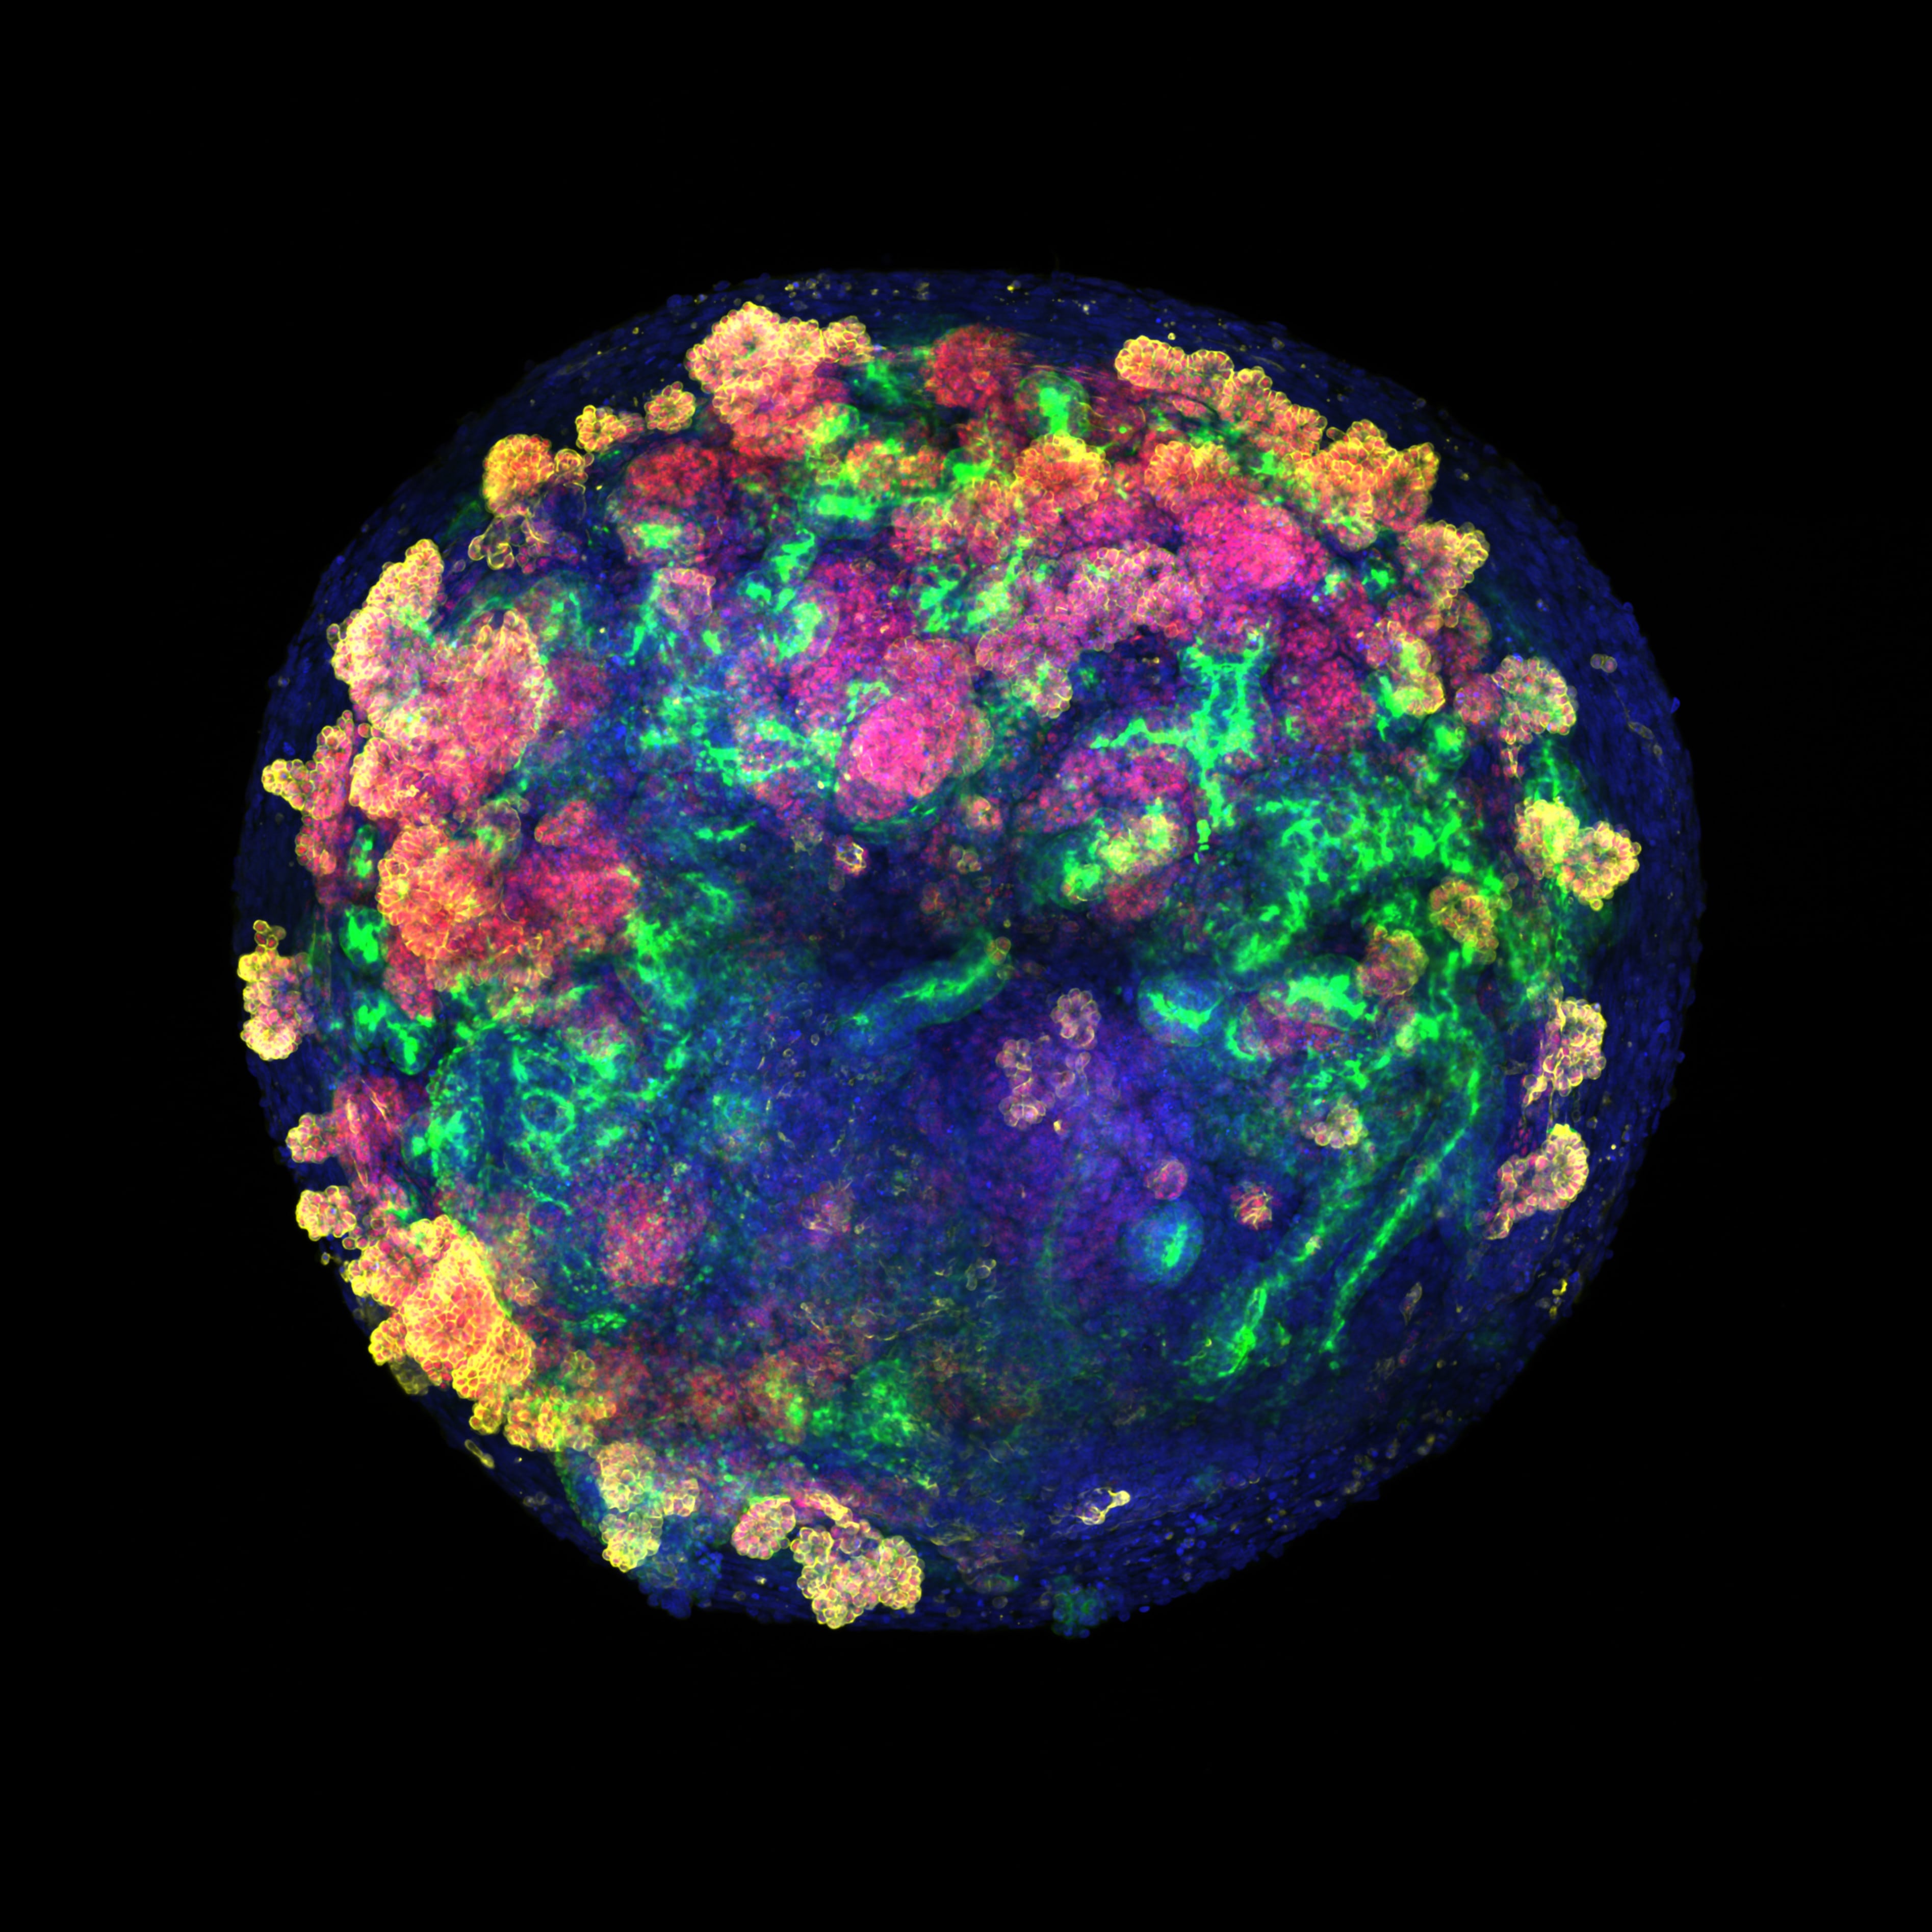

A pesar de que España es referencia mundial en trasplantes, cada año miles de personas se quedan sin recibir el riñón donado que necesitan. Lo mismo sucede con otros órganos. Y a nivel global el problema es muchísimo más grave, con millones de afectados y unas listas de espera que no dejan de crecer por el envejecimiento de la población. En Estados Unidos, diecisiete personas mueren cada día esperando un riñón trasplantado, y cada nueve minutos se suma un paciente más a la lista de espera. La situación amenaza con colapsar los sistemas de salud dentro de unos años. Hoy, un avance biomédico liderado por investigadores españoles abre una nueva vía para aliviar las listas de espera de trasplantes usando minirriñones humanos.Estos organoides empiezan siendo un amasijo de unas pocas células madre, y después crecen hasta ser unas pelotitas algo más pequeñas que la cabeza de un alfiler. En ese momento ya tienen un armazón de células especializadas que se asemeja al de los diferentes órganos del cuerpo, una característica que los hace ideales para estudiar enfermedades o hacer pruebas de toxicología.Más informaciónEl nuevo trabajo da un salto para explorar si estas estructuras también pueden usarse para trasplantes en humanos. Los investigadores han desarrollado organoides de riñón a partir de células madre humanas, los han cultivado y, por primera vez, han demostrado cómo producirlos en gran cantidad y de forma rentable, lo que acerca su futura aplicación a pacientes.El trabajo lo ha dirigido la bióloga barcelonesa de 47 años Nuria Montserrat, profesora de investigación ICREA en el Instituto de Bioingeniería de Cataluña (IBEC) hasta hace poco más de un año, y actual consejera de Investigación y Universidades de la Generalitat de Cataluña. Antes de asumir su cargo en el Gobierno de Salvador Illa, Montserrat llevaba más de una década impulsando el uso de estos cultivos celulares en medicina regenerativa. Ahora, junto a científicos de varias entidades españolas, incluida la Organización Nacional de Trasplantes, e investigadores de la Universidad de California, su equipo ha conseguido injertar por primera vez organoides renales humanos en riñones porcinos gracias a máquinas de perfusión normotérmica, utilizadas habitualmente en el quirófano para mantener el órgano vivo y oxigenado fuera del cuerpo antes de un trasplante. Esta maniobra permite la integración de las células humanas en el órgano del animal. Por primera vez, los investigadores han vuelto a trasplantar estos riñones a los animales vivos a los que se los habían extirpado, y han demostrado su funcionalidad y ausencia de rechazo. El estudio se ha publicado este viernes en la revista especializada Nature Biomedical Engineering.El paso siguiente, explica Montserrat a EL PAÍS, es ensayar la técnica con vísceras de cadáveres humanos. “Cada año se descartan más de 1.000 riñones que no son aptos para entrar en el proceso de trasplante. Ahora tenemos la oportunidad de usarlos para investigación”. El objetivo final es reducir las listas de espera de trasplantes y aumentar el número de riñones disponibles para su injerto.Fabricar organoides humanos que valgan para estos usos es complejísimo. “Hace 10 años”, detalla Montserrat, “nuestra idea era hacer un riñón humano entero, desde cero, pero es algo muy naíf”. “El riñón es uno de nuestros órganos más complejos, con 23 tipos de células especializadas diferentes”, añade. Dos médicos realizan el trasplante de riñón con organoides humanos en un cerdo vivo.IBECLos nuevos organoides renales son apenas visibles en el momento de integrarse en los órganos de cerdo —deben medir unas 200 micras para poder entrar por las arterias sin obstruirlas— pero ya tienen 19 tipos distintos de células específicas. Gracias a la colaboración con instituciones repartidas por España, que son el armazón de una futura red (desarrollo de miniórganos en Barcelona, experimentos y trasplantes al cerdo en A Coruña usando máquinas de perfusión fabricadas en Zaragoza, y análisis de la respuesta inmune en el Instituto de Salud Carlos III de Madrid), se ha demostrado esta técnica “como prueba de concepto”.La escasez global de órganos ha impulsado el uso de vísceras de cerdo para trasplantes en humanos. Hasta ahora, uno de los casos más exitosos había sido el de Tim Andrews, un estadounidense de 67 años al que se le injertó un riñón porcino que previamente había sido modificado genéticamente para eliminar virus y hacerlo más compatible con su organismo. La operación fue un éxito hasta hace apenas unos días, cuando los médicos del Hospital General de Massachusetts se lo extirparon porque estaba dando problemas. Andrews vivió 271 días con el implante, un récord mundial. Los dos primeros pacientes que recibieron estos trasplantes murieron poco después de la intervención, y el tercero pudo llevarlo durante 130 días hasta que su organismo lo rechazó. Otros pacientes vivos también han recibido trasplantes experimentales de corazón e hígado de estos animales, aunque su efectividad aún es muy incierta. Por ahora, este tipo de intervenciones se ven como un puente con el que ganar tiempo hasta que llega en órgano humano necesario.Los organoides humanos se suman ahora como una nueva vía, opina Jordi Ochando, inmunólogo del Carlos III y del Hospital Monte Sinai de Nueva York, y coautor del trabajo. “En muchas ocasiones un paciente no recibe uno, sino varios trasplantes de riñón debido al rechazo. Estas técnicas podrían ayudar a que los injertos sean más compatibles con el paciente y evitar problemas”, explica. Además, estos análogos “se pueden utilizar en riñones humanos que se descartan para trasplantar y aumentar el número de órganos disponibles, pero también se pueden utilizar en riñones de cerdos transgénicos para hacerlos más compatibles con el receptor”, detalla.Es la primera vez que se producen minirriñones de calidad en grandes cantidades y con una fiabilidad alta, destaca la bioquímica Elena Garreta, coautora del estudio. “Hasta ahora, con los métodos convencionales podías conseguir crear unos 40 tejidos de este tipo. Ahora, gracias a nuestro sistema, podemos fabricar 30.000 en un solo experimento, y además comprobamos que todos son de alta calidad”, señala. Aún quedan años de trabajo por delante, pero este avance abre muchas puertas hacia aplicaciones terapéuticas, opina.La nefróloga Beatriz-Domínguez-Gil, directora de la Organización de Trasplantes y coautora del trabajo, pinta el escenario de fondo en el que se encuadra esta investigación. “Un día cualquiera, en Europa hay más de 77.000 pacientes esperando un riñón para trasplante, según un estudio reciente en 40 países. Son gente abocada a un largo tratamiento con diálisis, con la disrupción que esto tiene en su desarrollo personal y profesional. Esto se transforma completamente con un trasplante renal, que mejora la esperanza de vida y además es menos costoso que la diálisis. Esta situación se complica con el envejecimiento progresivo de los donantes, que tienen mayor comorbilidad. Esto hace imprescindible buscar soluciones alternativas, y los organoides son una de las posibilidades de futuro”, expone. La directora de la ONT explica que ya existe un acuerdo con hospitales de Barcelona, Madrid, Galicia y Cantabria para empezar a usar órganos humanos descartados en estas investigaciones, previsiblemente el próximo año.Aunque la aplicación de estos tejidos humanos aún está lejos en el tiempo, opina Domínguez-Gil, la médico vaticina dos usos de esta tecnología: poder extirpar el riñón de una persona con patología renal, tratarlo con un sistema similar al empleado con cerdos y volver a implantarlo; y usar esta técnica para regenerar órganos donados que no cumplen los requisitos para trasplante.El médico brasileño Leonardo Riella fue el director del equipo que realizó el trasplante de riñón de cerdo al paciente estadounidense en el Hospital General de Massachusetts. El jefe de trasplantes renales y catedrático de la Universidad de Harvard, que no ha participado en este trabajo, lo alaba como un gran primer paso. “Es una prueba de concepto elegante e innovadora que demuestra que los organoides renales humanos pueden sobrevivir e integrarse dentro de riñones porcinos durante un corto período. Es un paso emocionante hacia la fusión de la medicina regenerativa y los xenotrasplantes [de animal a humano]. Los principales desafíos a futuro serán lograr una viabilidad a largo plazo y demostrar una verdadera función renal proveniente de los organoides trasplantados. Si se logra esto último, eventualmente podría conducir a nuevos tratamientos para restaurar la función renal en pacientes con enfermedad renal crónica”, destaca.Marcos López-Hoyos, jefe de inmunología del Hospital Universitario Marqués de Valdecilla, en Santander, advierte de que estas técnicas aún están en la fase de investigación en animales, pero aún así son “muy interesantes”. “En la actualidad ya se están recuperando riñones con métodos de perfusión ex vivo como los usados en este estudio. Los organoides, aunque no reproducen totalmente un riñón real, sí que son capaces de regenerarlo y tienen unas posibilidades enormes en tratamiento”, destaca.